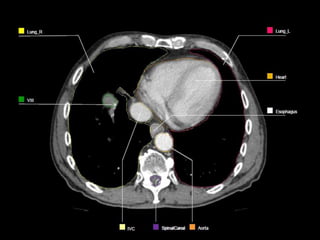

OARs  Liver  Kidney Stomach  Spinal Cord  Heart  Duodenum  Small Bowel  Lungs